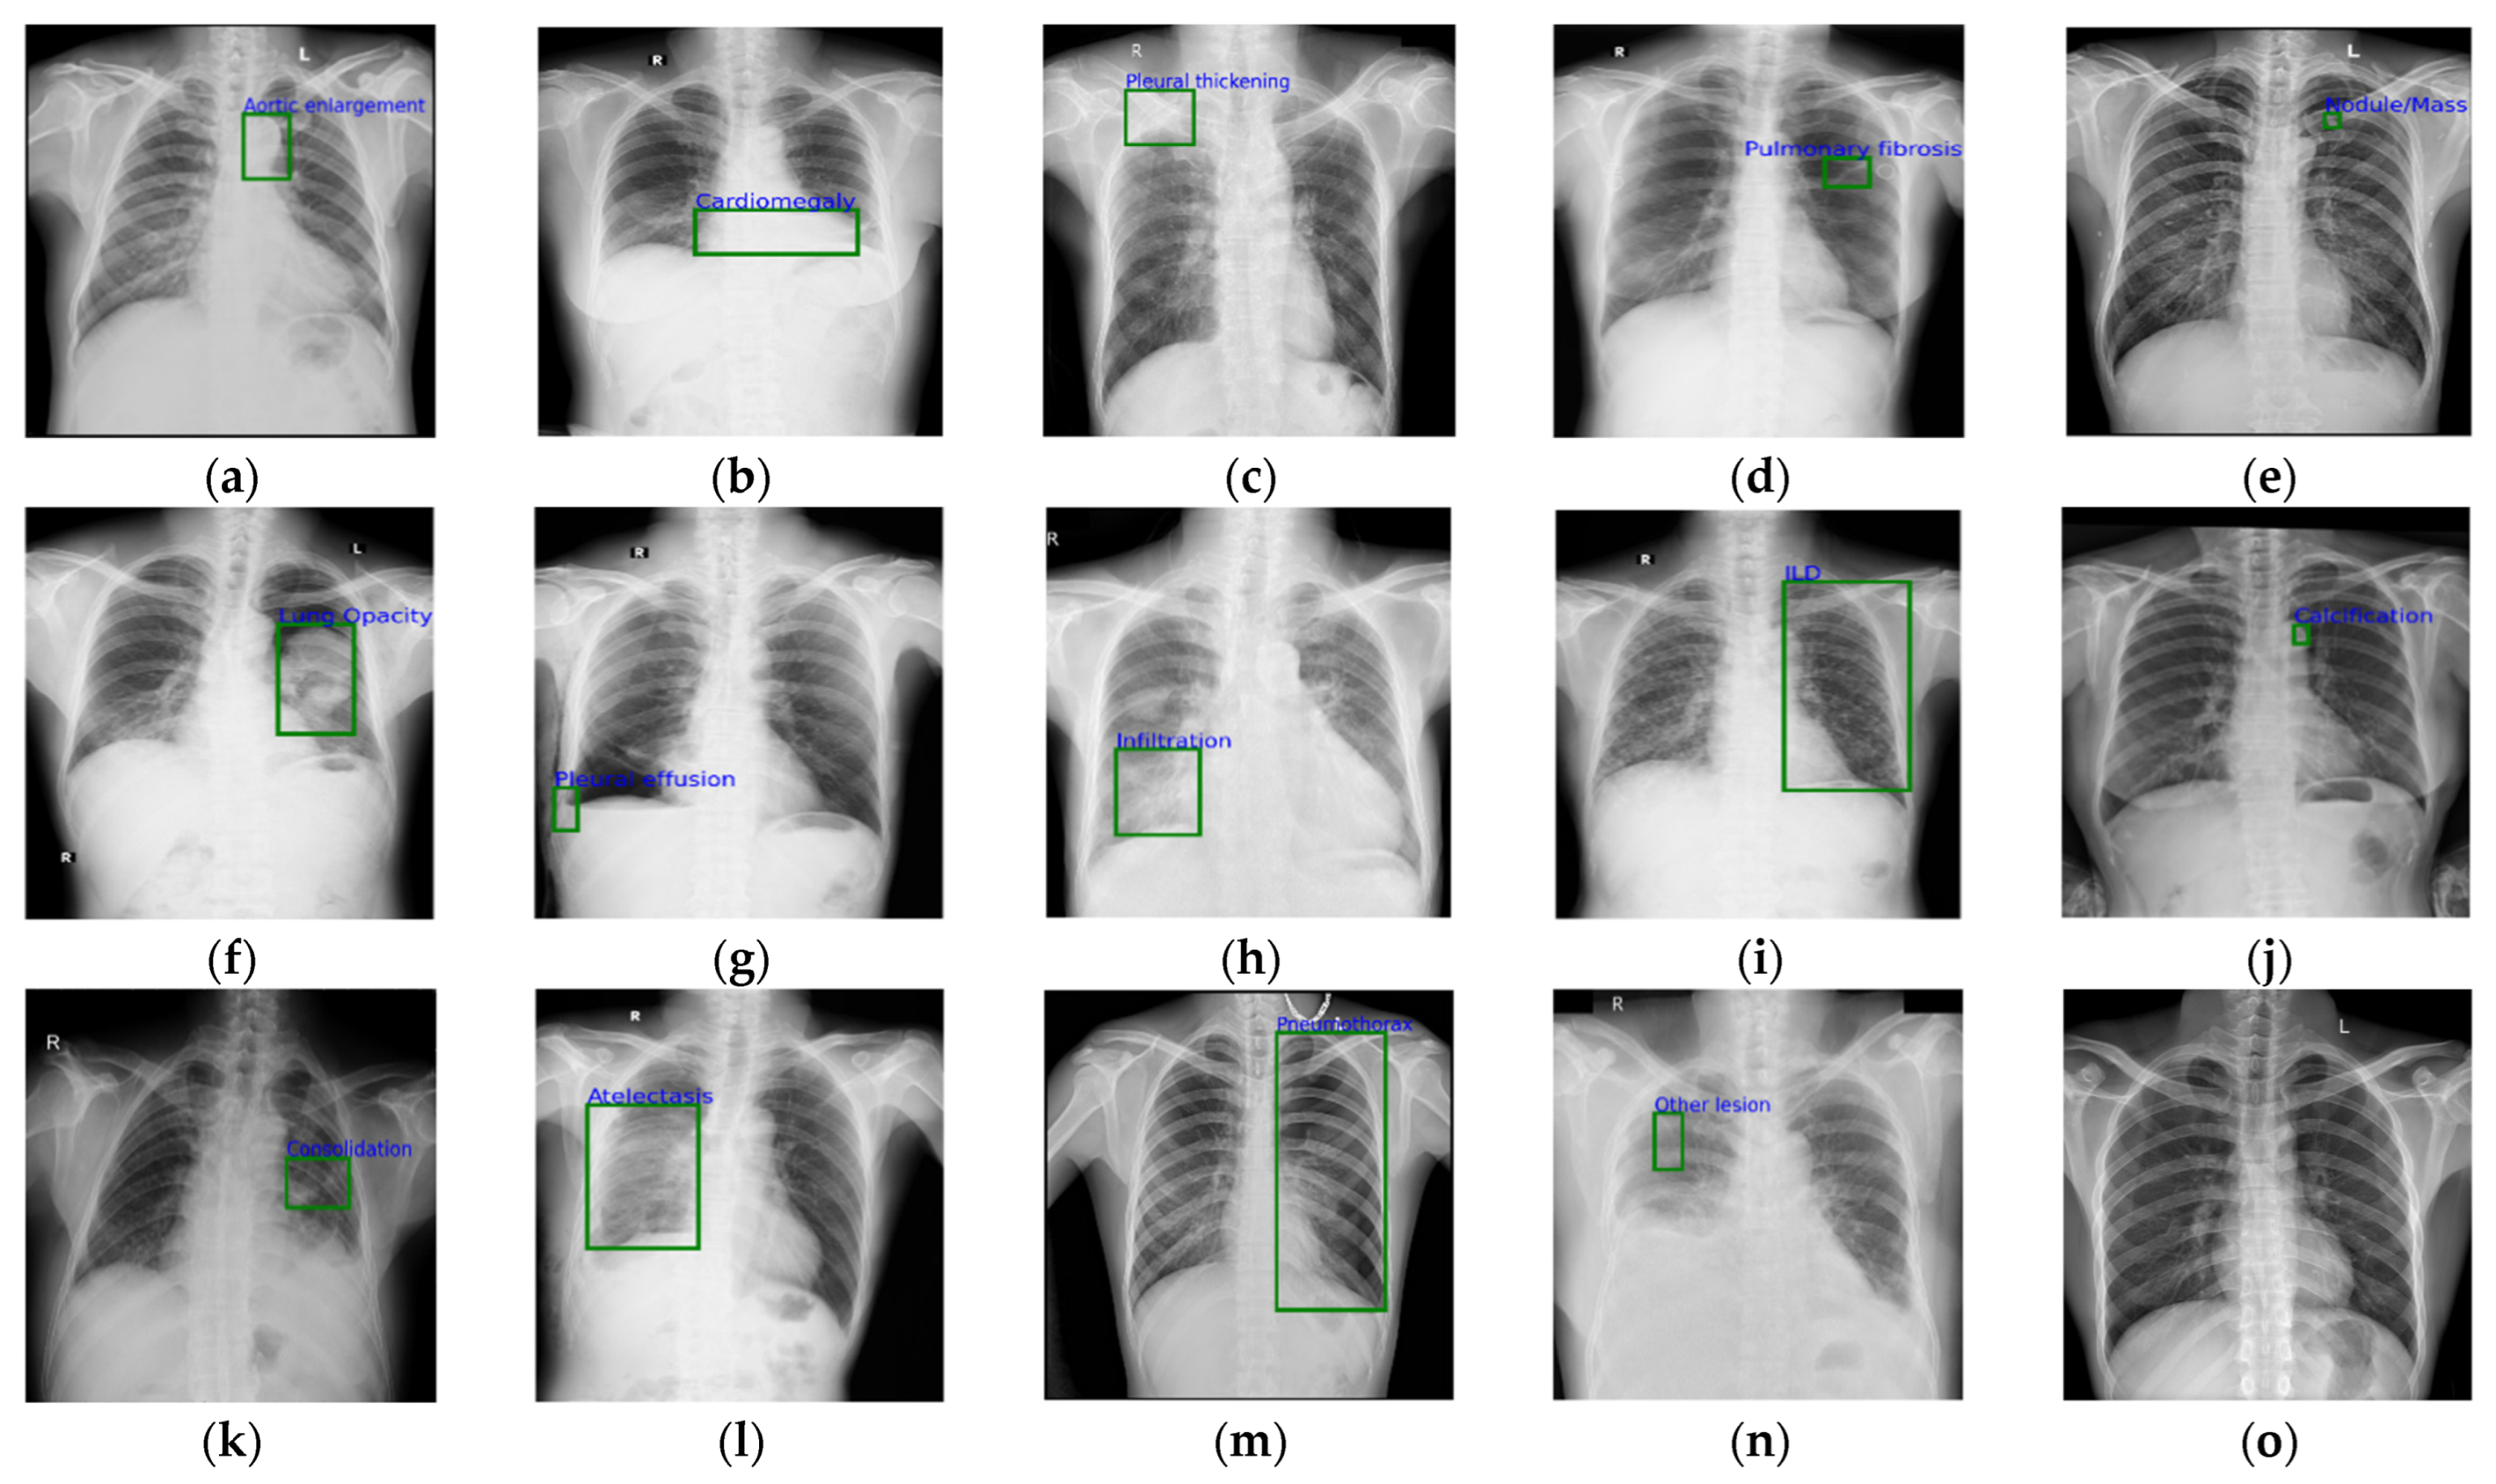

In this study, we used the VinDr-CXR chest X-ray dataset [41] collected from two hospitals in Vietnam for the experimental evaluation. A total of 15,000 images as the original data were provided to the academic community for scientific research, including 10,606 normal chest images and 4394 abnormal chest target images. The chest X-ray abnormalities in the VinDr-CXR dataset were further divided into 14 abnormal types. The number of each type is shown in Table 1, and sample images of the various types are shown in Figure 4. It is worth noting that the public dataset we used was published and peer-reviewed, where the X-ray images were processed and there was no privacy or harm involved. During our research, we also strictly followed the ethics of using medical datasets.

Figure 4.

Samples with different abnormalities in the VinDr-CXR dataset: (a) aortic enlargement; (b) cardiomegaly; (c) pleural thickening; (d) pulmonary fibrosis; (e) nodule/mass; (f) lung opacity; (g) pleural effusion; (h) infiltration; (i) interstitial lung disease; (j) calcification; (k) consolidation; (l) atelectasis; (m) pneumo-thorax; (n) other lesion; (o) normal.

By analyzing the distribution of the normal category and the other 14 categories with chest abnormalities in Table 1, it could be determined that the sample distribution among different categories in VinDr-CXR was very unbalanced and presented the characteristics of an obvious long-tailed distribution. The number of normal categories was too large compared with that of the other abnormal categories. If all normal images with more than 10,000 samples were taken as negative samples for training, the learning effect of the model was significantly affected. Therefore, we randomly selected 500 images from the normal category and 4394 abnormal images to form the final dataset, which was randomly divided into 80%, 10%, and 10% for the validation and test sets.